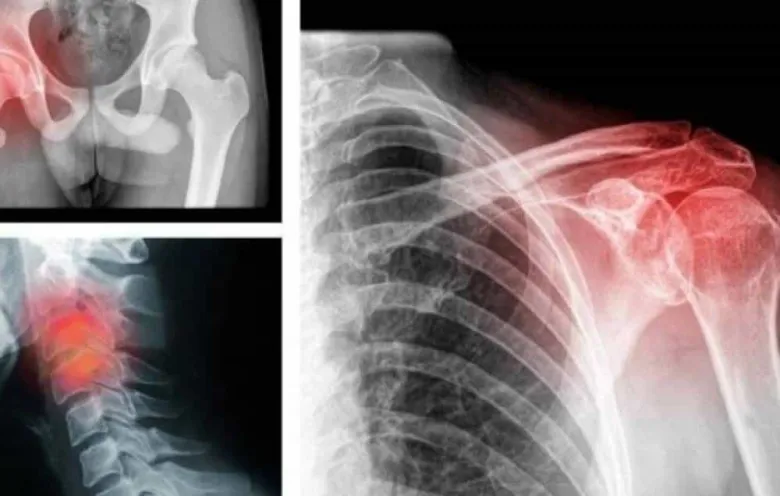

Շատ հաճախ մեր ցավերը կապված են ոչ թե այս կամ այն օրգանի խնդրի հետ, այլեւ նյարդերի։ Բժշկության մեջ վաղուց օգտագործվում է «փսիխոսոմատիկա» տերմինը։ Ահա 9 տիպի ցավեր, որոնք նյարդային ցավեր են՝ կապված նյարդերի եւ ոչ թե կոնկրետ հիվանդությունների հետ։

Գլխացավ

Գլխացավերն ավելի հաճախ լարվածության ու սթրեսի արդյունք են։ Թուլացրեք նյարդերն ու ազատվեք դրանցից։

Վզի ցավ

Վզի շրջանում ցավը հաճախ նյարդային սպազմի արդյուն է։ Ցավ ուսերում Սա այն բանի հետեւանք է, որ էմոցիոնալ առումով անչափ լարված ու ծանրաբեռնված եք։

Ցավ մեջքի վերեւի հատվածում

Թիակների ցավը կարող է նշանակել, որ հոգեբանորեն ընկճված եք։ Խոսեք ինչ-որ մեկի հետ, կիսվեք, ու այն կարող է անցնել։

Ցավ մեջքի ներքեւի հատվածում

Գոտկատեղի ցավերը կարող են նշան լինել, որ չափազանց շատ եք մտահոգվում գումար վաստակելու մասին։

Ցավ արմունկներում

Միապաղաղ կյանքը կարող է բերել նման ցավերի, նորություն մտցրեք ձեր կյանքում։

Ցավ ձեռքերում

Գուցե ձեզ մոտ շատ են բողոքում, նվնվում, եւ ուրիշների խնդիրները փոխանցվում է ձեզ՝ այսկերպ արտահայտվելով։

Ցավ ազդրերում

Ազդրերի խրոնիկ ցավը լարվածության ու վախի արդյունք է։

Ցավ ծնկներում

Սա նշան է, որ չափազանց մեծ ծանրություն եք վերցնում ձեզ վրա։

Սովորեք թուլանալ, հաշտվեք այն ամենի հետ, ինչ չեք կարող վերահսկել ու սովորեք երջանկանալ փոքրիկ բաներով։ Դուք էլ չեք զգա, թե ինչպես են բազմաթիվ ցավեր լքում ձեզ։